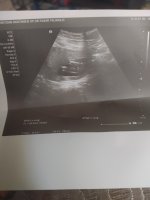

Ultrason resimi bakabilir misin cinsiyeti tahmin edin kizmi erkek mi

IMG_20220214_113511.jpg

717.2 KB · Görüntüleme: 14

Canım gönlüne göre olsun inşallah pek anlamasam da kız diye tahminde bulunayım

Kız gibi

Evet kızdır doktor dedi de hayırlısı olsun inşallah

Ne güzel kız evlat bambaşka anneye arkadaş dert ortağı